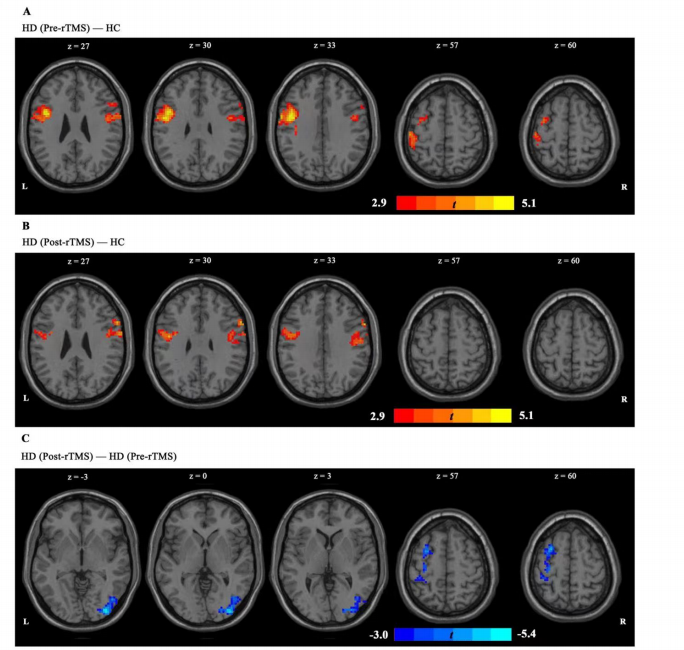

上圖為經顱磁刺激后左側 IPL 與全腦網絡之間的功能連接,采用雙樣本t檢驗。A圖顯示,與 HC組相比,HD(治療前)組左側IPL-左中央前回偶聯和左側IPL-右額下回耦聯增加。B圖顯示,經rTMS治療后,HD組左IPL-左中央前回耦聯和左IPL-右額下回耦聯異常增加明顯減少,在完成 7 個療程的 rTMS 治療后,呈接近HC組的趨勢。C圖顯示 rTMS 對左側IPL-左側額中回偶聯和左側IPL-右側枕下回耦聯有顯著影響。在這兩個區域,經過 7 次經顱磁刺激療程后,功能連通性顯著下降。

上圖為經顱磁刺激后右側 IPL 與全腦網絡之間的功能連接。

A圖顯示,HD組(治療前)的右側 IPL-左側中央前回偶聯和右側 IPL-右側中央前回偶聯均有所增加。B圖顯示,在 7 個療程的經顱磁刺激后,這些異常增加的連接減少了